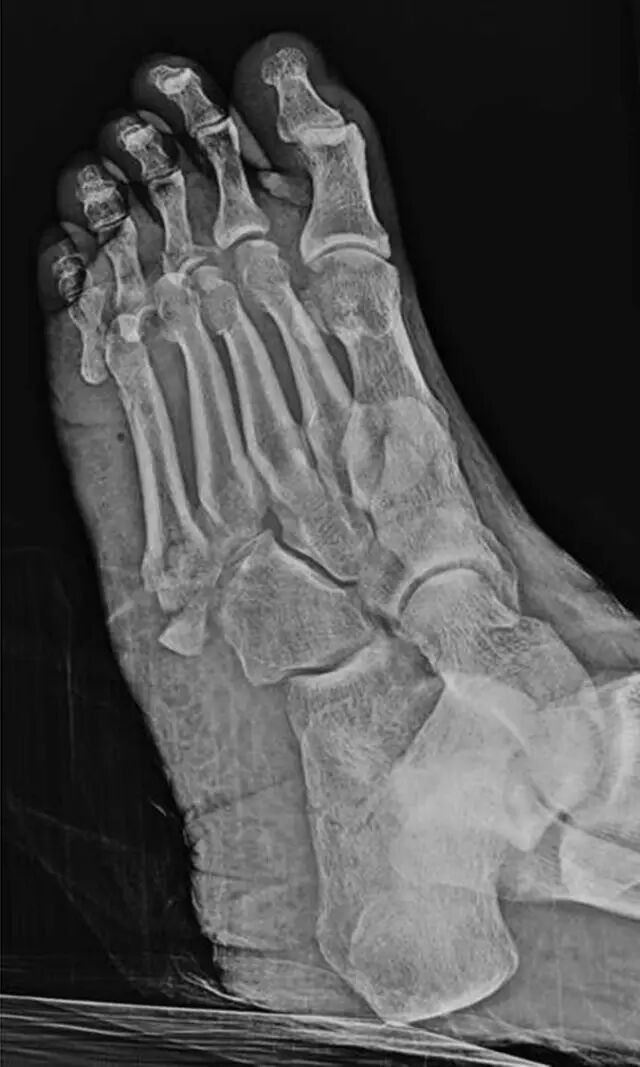

图 9A-61岁的女性在机动车辆碰撞中多发性创伤。多发性骨折脱位导致Satisfaction of SearchA,初步评价足前侧倾斜(A)和侧向(B)足部X线照片对多发跖骨和足趾骨折和多发跖趾关节脱位。最初忽略了跟骨骨折。

怎么取放射片研究--浅析下肢创伤中容易漏诊的X线片_https://www.jmylbn.com_新闻资讯_第24张

图9B-61岁的女性在机动车辆碰撞中持续多发性创伤。多发性骨折脱位导致搜索的满意度。B,初步评价足前侧倾斜(A)和侧向(B)足部X线照片对多发跖骨和足趾骨折以及多发跖趾关节脱位。最初忽略了跟骨骨折。